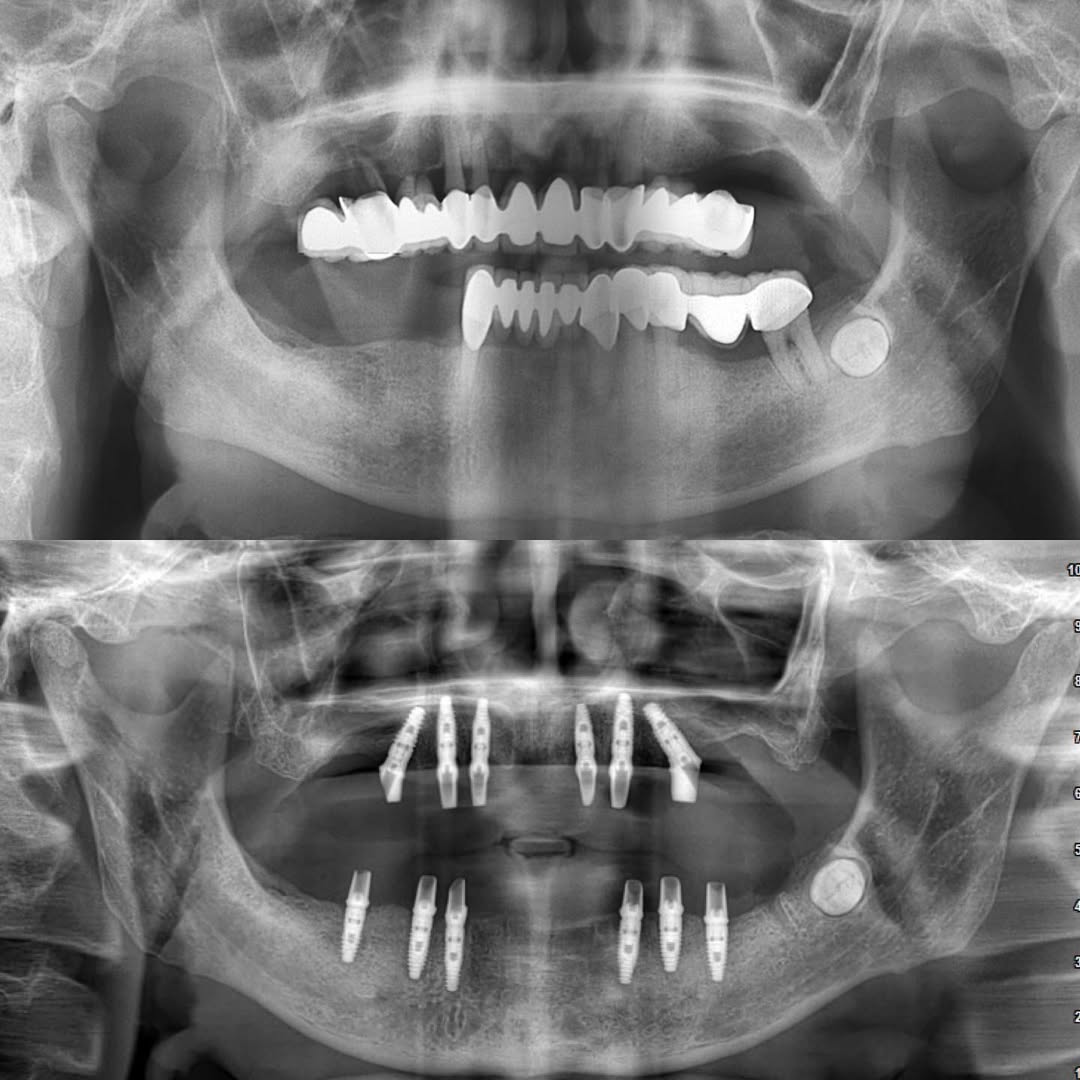

- Kaplama, şekil ve ağız içi pozisyon bozukluğu olan ve ortodontik tedaviye başvurulmayan dişlerde

- Dolgu malzemesi ile tedavi edilemeyecek büyüklükte doku kaybı olan dişlerde